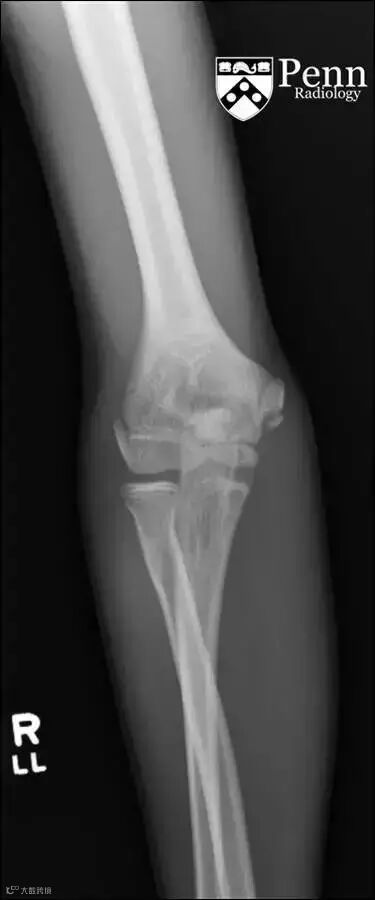

右肘关节正位X线片

平片:肱骨内上髁骨骺板增宽、分离,但无撕脱。